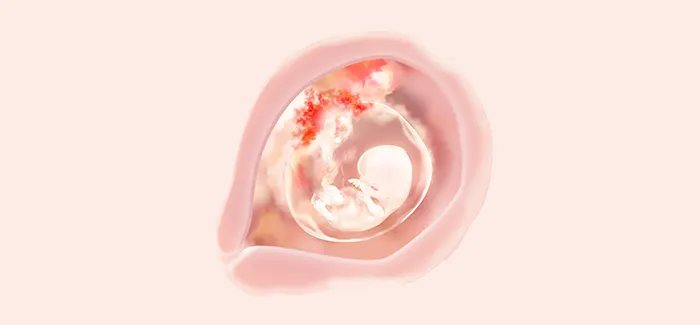

השבוע, הקטנטן שלך (שכעת כבר נחשב רשמית לעובר) נראה פחות ופחות כמו כתם ורוד – בייחוד מאז שהזנב שלו נעלם סוף-סוף. כשגופו כבר מאורך ומיושר, אורכו של הקטנטן שלך הוא כבר כ- 2.5 ס"מ.

זהו שלב קריטי בהתפתחות תקינה של הידיים והרגליים. הרגליים התארכו והניצנים שיהפכו בסופו של דבר לבהונות החלו לבצבץ. גם הזרועות התארכו בינתיים והחלו להתקפל באזור המרפק. גם מבנה יד בסיסי נוצר והוא כולל את האצבעות והאגודל המופרדים כבר באופן ברור. הכבד של הקטנטן שלך, כיס המרה, הטחול ובלוטת הכליה מתחילים להתפתח.

בשבוע ה-9 להריון, הקטנטן שלך כבר בתנועה מתמדת. זוהי תחילתה של תקופת הריקוד שלו, עם תנועות נמרצות המתרחשות באופן ספונטני בתגובה לגירויים מבחוץ, כגון אור ורעש. התאזרי בסבלנות – תצטרכי לחכות עד לשליש השני כדי להרגיש את התנועות האלו ממש.